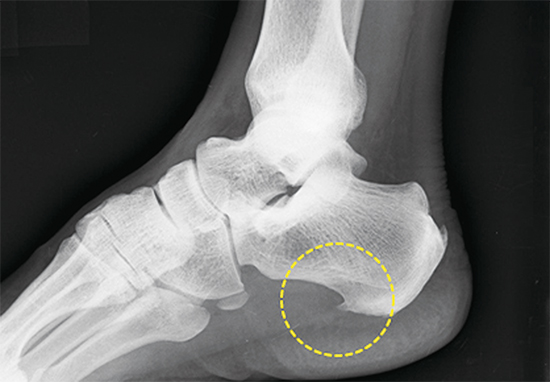

플랜타르 패시아염 (족저근막염)

- 발바닥의 아치에 위치한 두꺼운 섬유 조직인 족저근막이 염증이 생기는 질환입니다. 주로 장시간 서 있거나 걷는 경우, 혹은 비만으로 인해 과도한 압력이 가해져 발생합니다. 통증은 주로 아침에 일어났을 때 첫 발을 내딛을 때 가장 심하게 느껴지며, 점차 운동 후에도 나타날 수 있습니다.